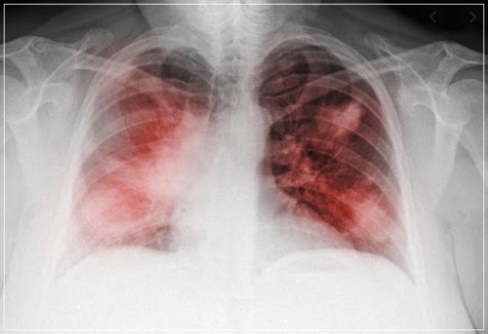

폐렴에서 비롯되는 패혈증, 감기와 구분해야

패혈증은 다양한 질환이 기전이 될 수 있습니다. 초기 증상이 나타날 때, 패혈증으로 이어질 수 있는 폐렴인지 감기인지 헷갈릴 수 있습니다. 감기는 보통 급성으로 일주일 이내로 증상이 나타났다가 호전되는 것이 대부분입니다.

폐렴은 시간이 지나도 고열이 계속되고 호흡곤란과 몸 상태가 급격하게 나빠지고 항생제 치료를 하더라도 반응이 없고 호전되지 않습니다. 폐렴에서 패혈증으로 악화될 때는 초기에 매우 급격하게 진행되는 경우와 일반적인 폐렴 증상이 지속되다가 패혈증이 발생하는 경우로 나뉩니다.

폐렴에서 매우 급격하게 패혈증으로 진행하는 전자는 증상이 확연해 바로 병원을 방문하기 쉽지만 문제는 후자의 경우로 이때는 단순 감기인지, 패혈증으로 악화될 수 있는 폐렴인지 구분이 쉽지 않습니다.

이러한 경우 전문의의 진찰 및 흉부영상촬영 등을 통해 감별해야 합니다. 감기 증상이 수일간 지속될 때는 병원을 즉시 방문해야 하는 이유입니다.